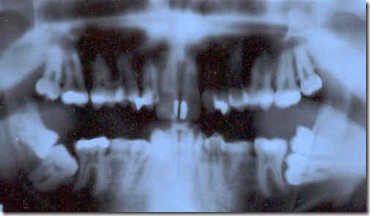

Una imagen de rayos x del diente, mostrando todo el diente (llamado radiografía periapical). Esto servirá al dentista de referencia durante el procedimiento.